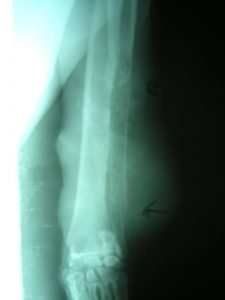

Se recomienda realizar un diagnóstico acompañado de radiografías de la lesión y un estudio histopatológico. Cuando no exista concordancia entre los resultados de el estudio citológico con los resultados del estudio histopatológico la recomendación diagnóstica del autor es guiarse por el resultado de la prueba citológica. El diagnóstico simplemente radiográfico es posible y es materia de los radiólogos y traumatólogos veterinarios.